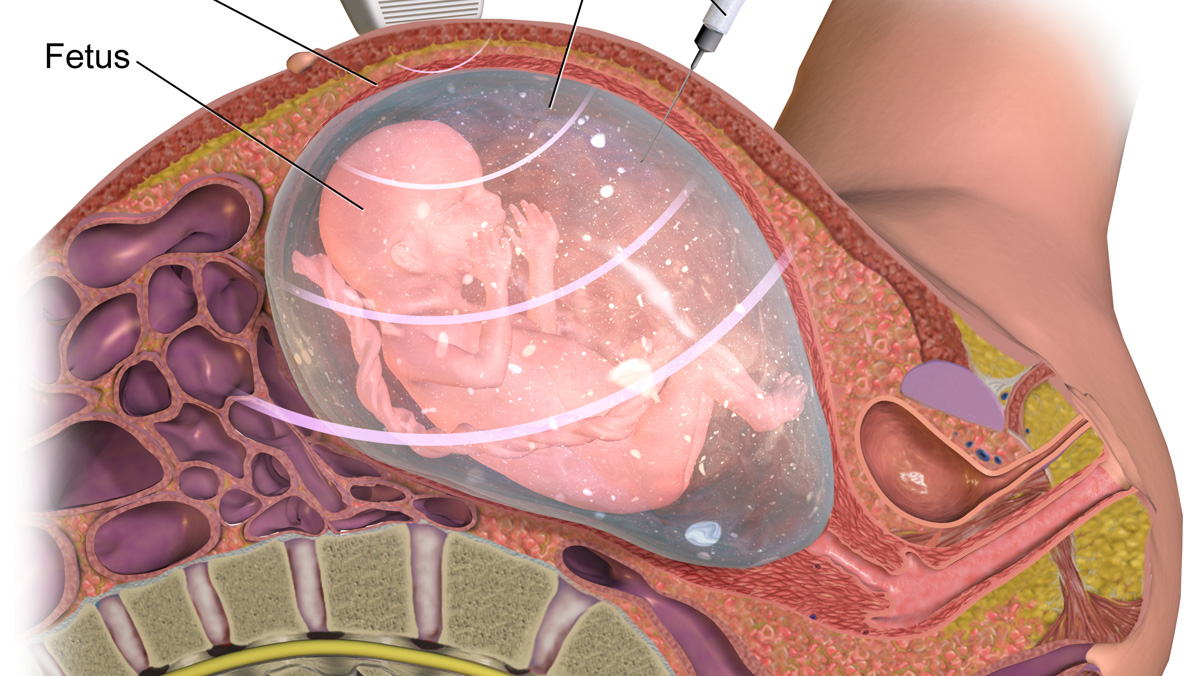

Амнион и Околоплодные Воды: Функции и Роль в Беременности